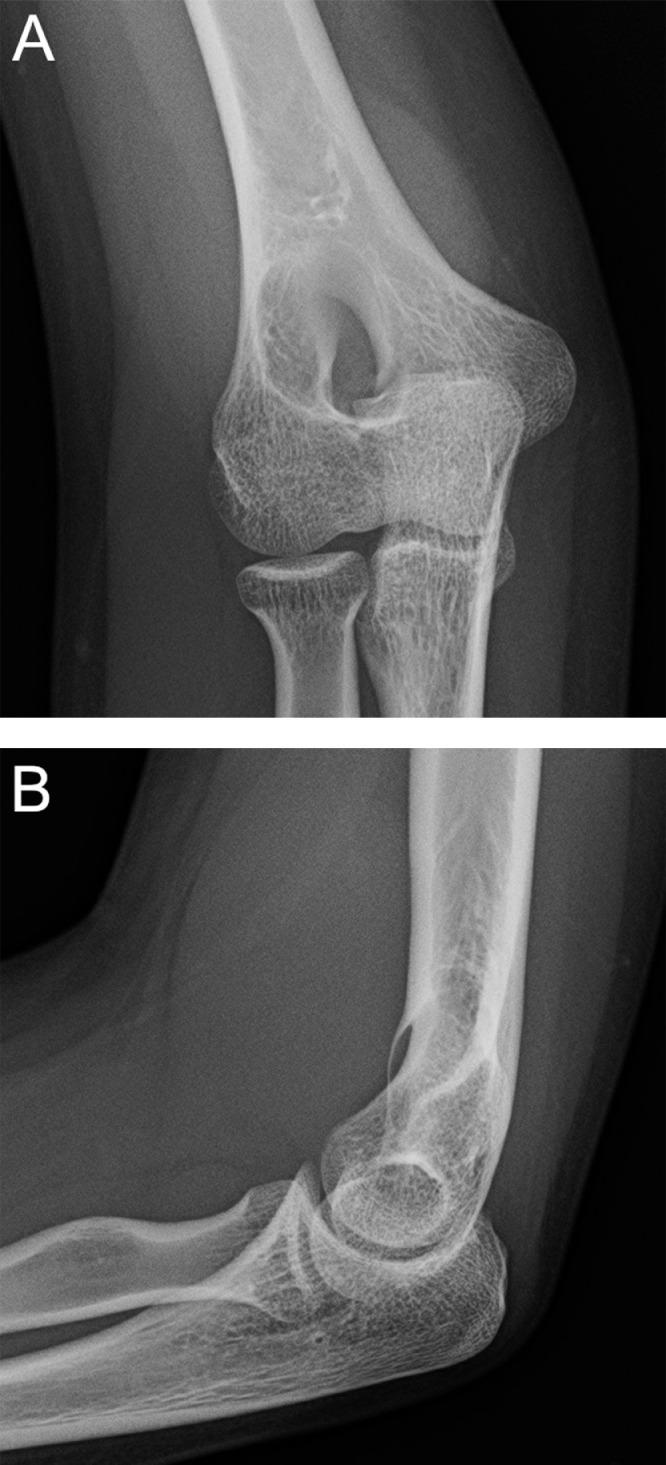

Partially intraosseous schwannoma of the distal humerus with increased enhancement after biopsy: Radiologic-pathologic correlation.

Intraosseous schwannomas are rare benign tumors that most often occur at the mandible or sacrum. We present an unusual case of a bilobed schwannoma of the distal humerus with both intraosseous and extraosseous components. The extraosseous component was non-enhancing on initial MRI and enhanced on a subsequent MRI obtained after biopsy. We hypothesize that this change was attributable to decreased intra-tumoral pressure secondary to biopsy-related disruption of the tumor capsule.